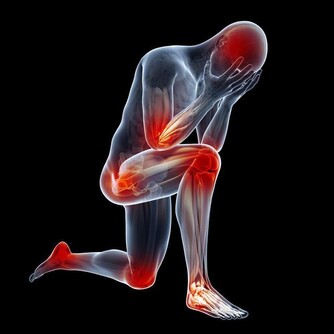

3身體疲乏,越來越瘦

很多肝癌患者,問他什麼感覺,他就唉聲嘆氣地說累,沒勁兒。很多人體力活動後也會很累,但這個累,休息後就能緩解。而肝癌患者的累,確實長期無法緩解的,即使睡眠很充足,仍然覺得很疲憊,很累,甚至連吃飯的力氣都沒有。這是因為肝細胞大量損害,導致營養吸收不良產生的。而腫瘤增大,也會和身體爭奪營養,導致身體越來越瘦。